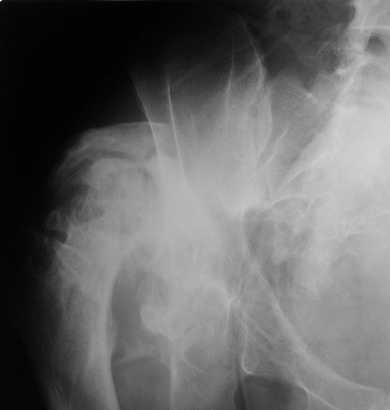

Пациент 30 лет 3 года назад в результате травмы получил травматический

дефект нижних конечностей до в/3 голеней, был пропущен вывих бедра. В настоящее время очень

неплохо ходит на протезах, движения в неоартрозе близки по объему к здоровой стороне.

Основная жалоба - выраженная боль при ходьбе. планируем двухэтапное эндопротезирование -

задним доступом мобилизовать проксимальный отдел бедра, резецировать шейку, аппаратом

низвести бедро(головку оставить там где она есть, так как больших дефектов не видно(может

пригодится в последующем?)). Вторым этапом бесцементное эндопротезирование. Насколько

такой вариант реалистичен? Доступ для второго этапа? Может быть, другие варианты?